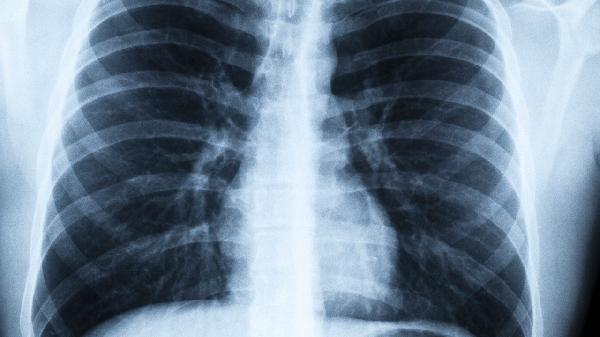

你以为的精致生活,可能正在悄悄摧毁你的肺。那些看似优雅的习惯,背后藏着的健康隐患比你想象的更可怕。某三甲医院呼吸科医生曾提到,门诊里越来越多年轻患者拿着CT报告单崩溃大哭,而这些病灶往往与他们的"精致日常"密不可分。